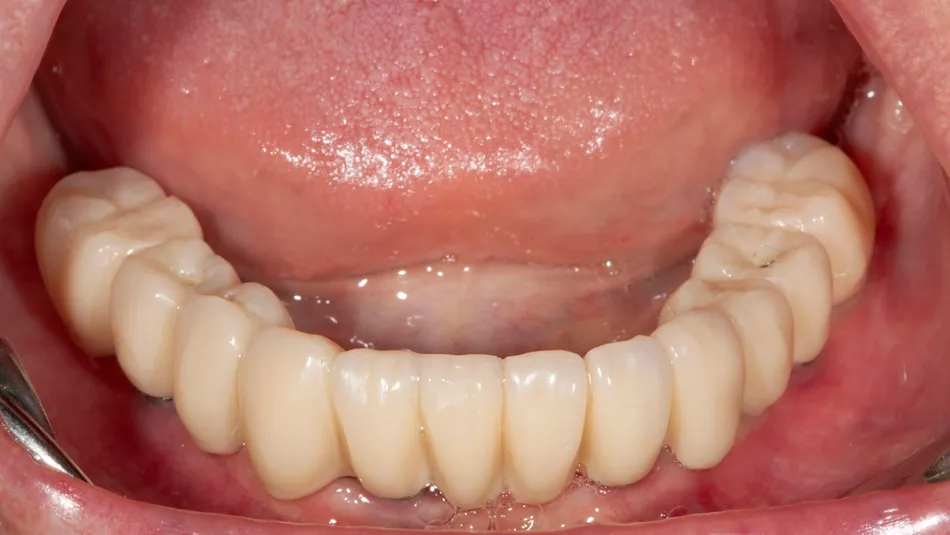

13. Occlusal pictures of healing around the implants at 3 months follow-up upon removal of the provisional prosthesis.

16. Display of the finished lower jaw work after osseointegration.